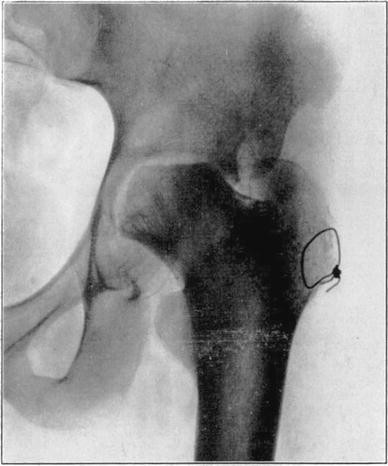

Case 1. Two hundred and fifty days after operation. Head extensively reduced in density from invasion and replacement from the living bone of base of neck.

Case 1. Four hundred and four days postoperative Cavitation at base of head and further transformation.

The hip showed about forty degrees of flexion but marked limitation of abduction and rotation. Its strength had gradually improved and there was only slight discomfort in walking unless it was prolonged.

The cause for this exceptional occurrence of necrosis of head and neck without sequestration appeared to lie in the traumatism of head and denudation of neck of its covering of soft parts. However, it may have been due in part to deep-seated mild infection in the region of the new joint, despite the absence of discharge from that region. Failure of the necrotic head to be sequestrated speaks decidedly in favor of aseptic instead of septic necrosis although sequestration may not occur in the presence of mild infection of a necrotic area. In another case I observed necrosis of the head and neck following an arthroplasty in which there was infection of the wound with a purulent discharge, but the dead bone was sequestrated in the course of several weeks. In the case here reported functional stimulation of the bones resulting from movement of the joint, combined with protection of the necrotic head from weight-bearing, was followed by creeping substitution of the necrotic bone by new bone in the greater part of the head without either erosion of dead bone or the development of marked deformity.